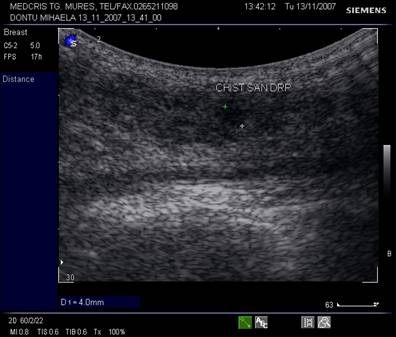

Criterii ecografice pentru chistul mamar

forma rotunda/ovalara

margini bine delimitate, netede

omogenitatea

anecogenitate sau hipoecogenitate

aparitia fenomenului de intarire acustica posterioara

Fig, nr. 340. Chist al sanului